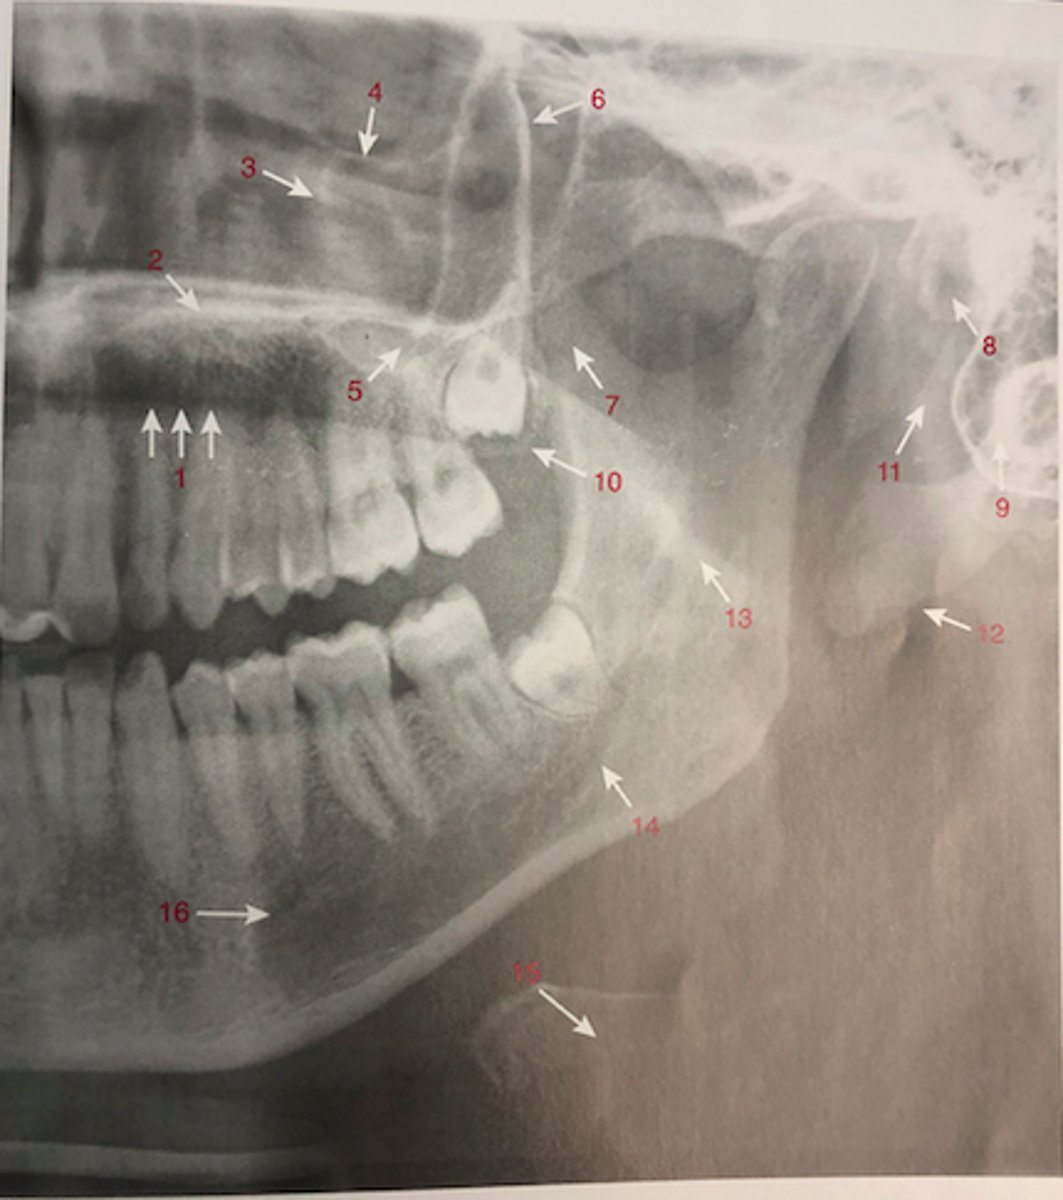

2. Identify the normal anatomic landmarks labeled 1 - 16 in figure 29-15

Identify the normal anatomic landmarks labeled 1 - 16 in figure 29-15

palatoglossal air space

1

hard palate

2

infraorbital foramen

3

floor of the orbit

4

zygomatic process

5

posterior wall of max sinus

6

zygomaticotemporal suture

7

external auditory meatus

8

lateral pterygoid plate

9

max tuberosity

10

styloid process

11

soft tissue of ear

12

mandibular canal

13

cervical spine

14

hyoid bone

15

mental foramen

16